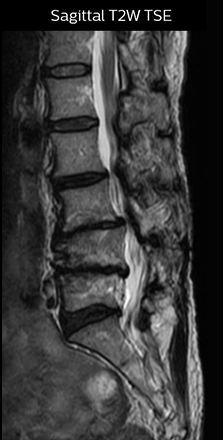

“For example, in sagittal images, when the presence of fat is observed in the intervertebral foramen, it suggests that there is a margin around the nerve. Similarly, the absence of fat indicates that the nerve is being compressed. So, we used to deduce nerve compression indirectly. With NerveVIEW, however, we can observe the condition of the nerves directly, regardless of the presence or absence of fat. We always prefer such direct observation of anatomy over having to make an inference about it.”

“The intra-luminal signal of veins, especially around the intervertebral space, can be suppressed well with NerveVIEW. As a result, we can easily observe the detailed nerve structure around the posterior ganglion,” he says. “This is why we use 3D NerveVIEW for intraforaminal stenosis and extraforaminal stenosis/herniation (lateral disc herniation). On the other hand, if herniation is suspected to exist inside the dorsal root ganglion (DRG), balanced TFE or ProSet-FFE is applied. NerveVIEW is not suitable for evaluating the median type of herniation.” The SE-EPI DWI-based method for MR neurography works well for large FOV exams like whole-body MRI, but focal examination of nerves is often limited by the attainable spatial resolution (both inplane and slice direction) and geometric distortion. “3D NerveVIEW achieves higher in-plane resolution – close to our other routine spine sequences – and the source images can be used instead of adding a fat-suppressed T2-weighted sequence,” Tanji says.

“For both brachial and lumbar plexus, we are currently using a 230 mm FOV and voxels of about 1 x 1 x 2 mm acquired (1 x 1 x 1 mm reconstructed). This provides us a good representation of the nerves, even though this FOV is relatively small. Regarding the inplane resolution, we hope to be able to bring that down to 0.7 mm, similar to our typical 2D multislice T2W images,” says Tanji.

Implementing NerveVIEW without lengthening exam time “The source images of NerveVIEW exhibit a contrast similar to STIR or fat-suppressed T2-weighted images. So, in our neurography exams we are replacing the 2D T2-weighted coronal sequence with 3D NerveVIEW. With this, we add a lot of useful information without adding scan time. This is important for patients with severe lower extremity symptoms, as they often find it difficult to maintain still during the whole MRI examination, so the exam should be as short as possible.” “We have currently implemented 3D NerveVIEW on our Achieva 3.0T dStream MRI system only. Because the 3D NerveVIEW method is based on a background signal suppression technique, we decided to use the high SNR of our 3.0T MRI system for obtaining the best possible visualization of peripheral nerves,” says Tanji. “Where NerveVIEW of the lumbar plexus is currently used as a subroutine scan for patients with strong lower limb symptoms, its use for visualization of the brachial plexus, is currently limited to special cases such as schwannomas and neuritis, usually only 1 or 2 cases per month.”